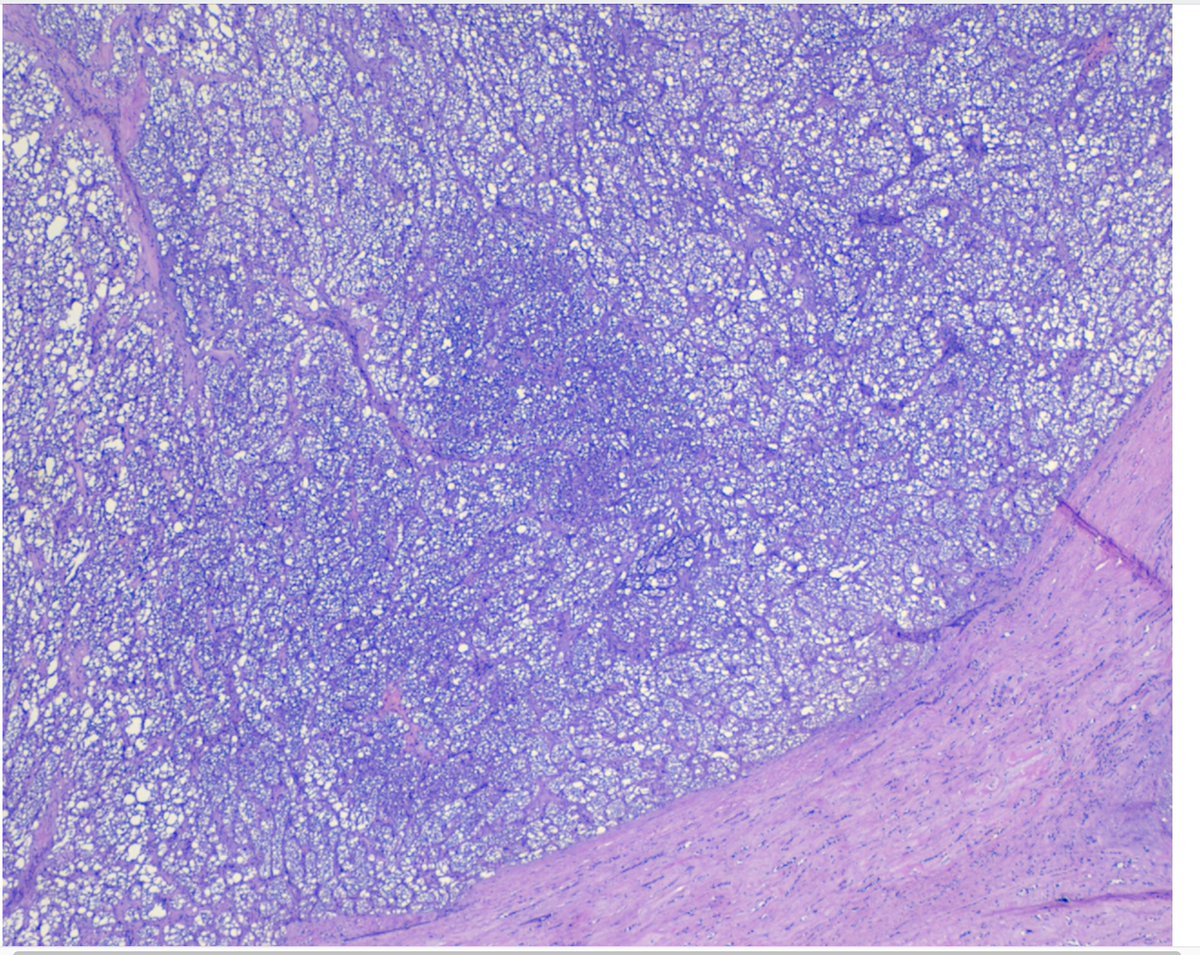

#MTPathUnknown #268

Slide 1 of 3

Incidental mass in decomposed individual.

Slide 2 of 3 is close-up of mass

Slide 3 of 3 is the organ.

What is the most likely diagnosis (based upon common things being common)?

Challenge: can you make diagnosis without slide 3?

@WKemp_MT_FPDoc Clear cell renal cell carcinoma (ccRCC), cells with clear cytoplasm and nested pattern.